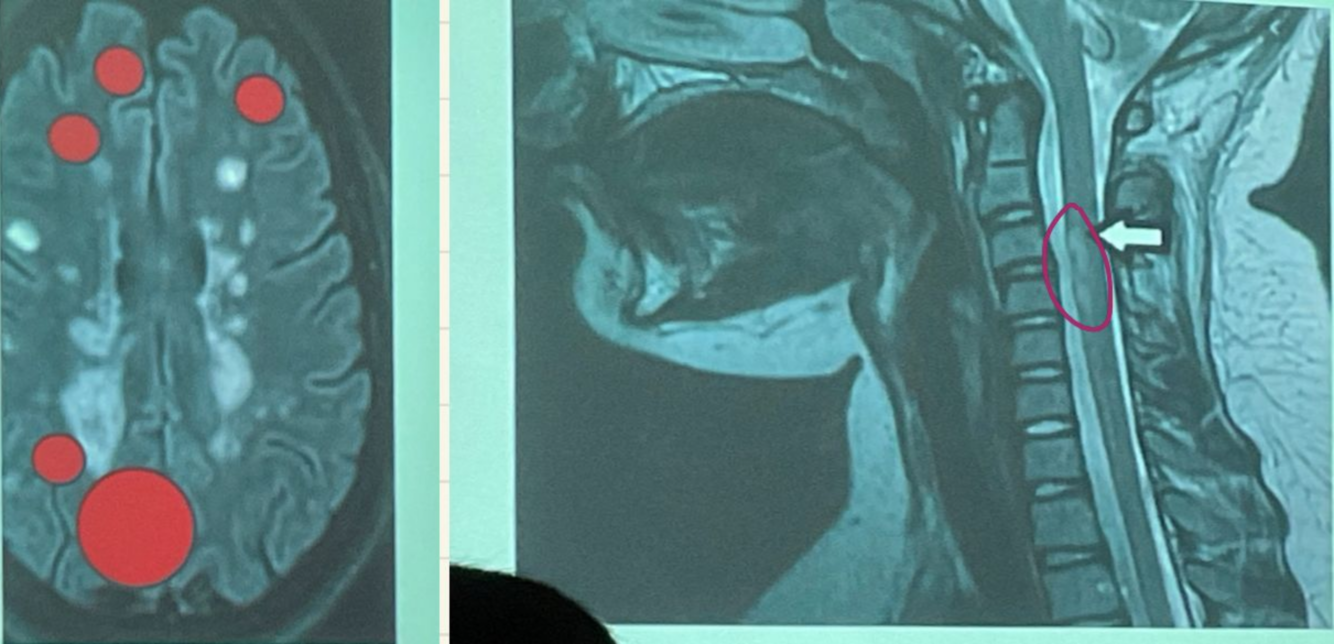

En la resonancia magnetica la esclerosis multiple da estos signos:

A

Hiperintensidad en T2 y FLAIR

Hipointensidad en T1

Lesiones redondas y ovaladas, bordes definidos menores a 5mm

La lesiones en imagen de la esclerosis multiple estan ubicadas en regiones cercanas a corteza cerebral

Yuxtacorticales Periventriculares Tallo cerebral Medula

Una mielitis corta es considerada como tal cuando la afeccion es de:

Menos de 3 vertebras (sera larga cuando sea mayor a 3 vertebras)